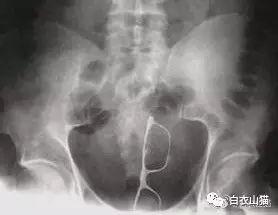

一般情况下,这些肛门异物的病人,来到医院后,医生都会给他上麻醉。把病人麻醉后,在透视下从肛门里夹取直肠里的东西。

一般情况下,用产钳可以取出大部分直肠异物。

如果从肛门里取不出,那就要开膛破肚了。